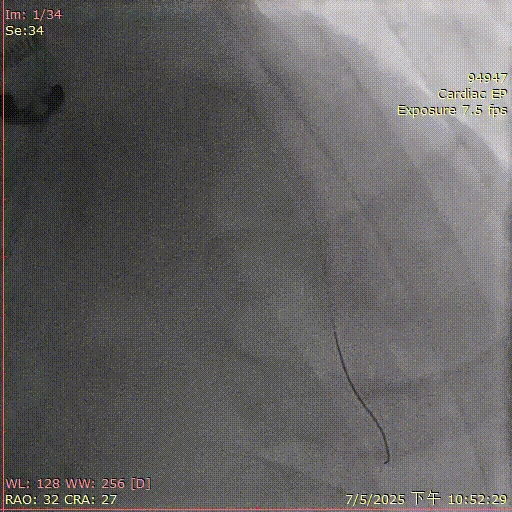

术前造影

术后造影